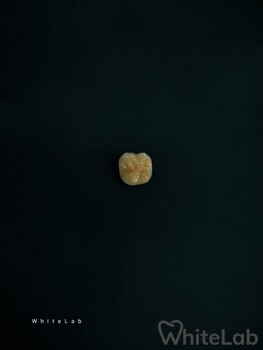

Мы изготавливаем безметалловые виниры и коронки методикой прессования керамики, фрезерование керамики и циркония для создание полной анотомии зуба. Так же используем технику нанесение керамики на рефракторе, при которой слои керамики укладываются послойно, у зуба восстанавливается полная анатомия и он выглядит как натуральный.

Данные методики дают возможность получить естественный, яркий, блестящий вид винирам, коронкам, которые создают самые естественные, реалистичные преобразования улыбки, которые могут быть достигнуты современными технологиями.